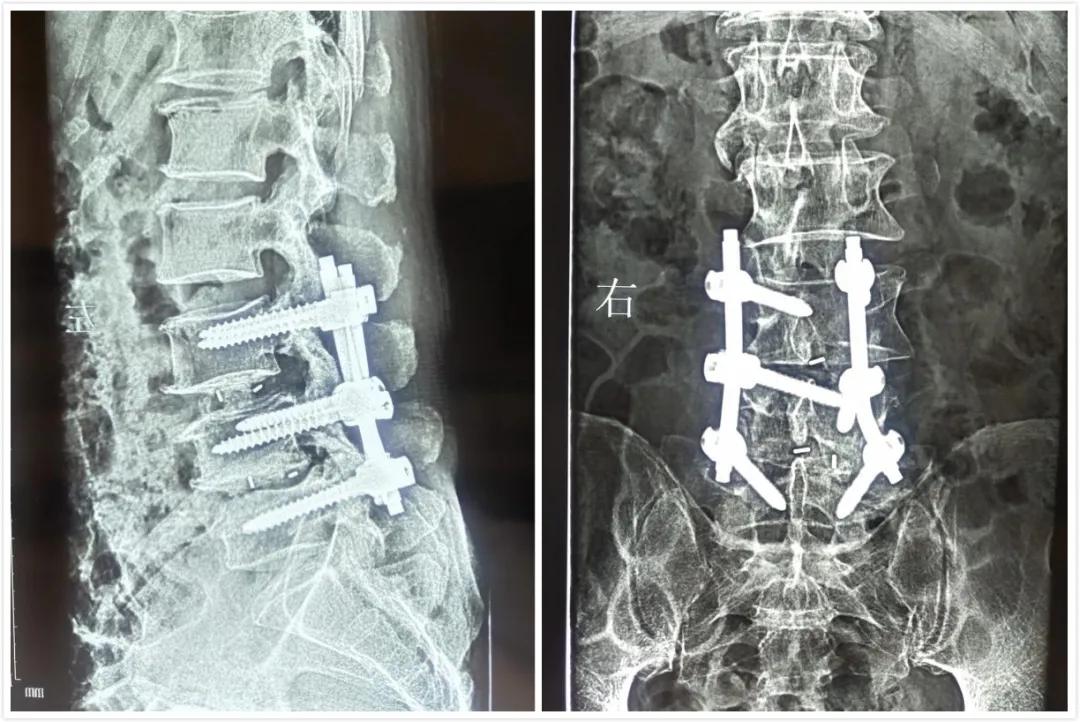

汤宁院长仔细询问病情后,建议李先生做DR检查。DR片显示,腰椎退行性变并腰椎椎体不稳,L4-5椎间盘病变。为进一步治疗,以“脊柱不稳”收住院,予以脊椎融合、固定。术后,在骨科副主任贾玉章、护士长李俊杰等医护人员的精心治疗和照护下,身体恢复很快,病情明显好转,10天后顺利出院。